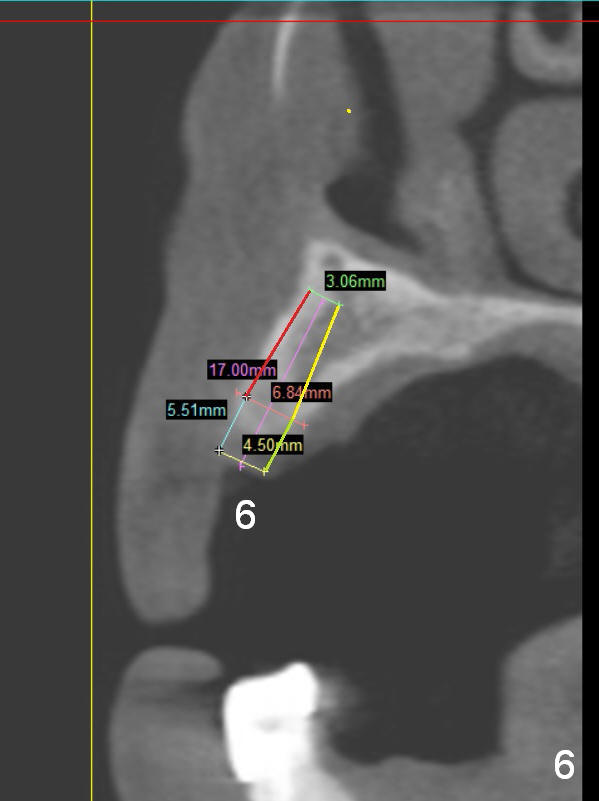

A 68-year-old lady has several missing teeth (Fig.1,2).  She has agreed to have an implant at the site of #3 (Fig.3) to stabilize an upper removable partial denture (RPD).  The latter will be more stable if an extra implant is placed at #6 (Fig.1,2,6).  There is enough bone to place implants at #4,5 (Fig.4,5).  Bone density at these sites is low.  Osteotomy should be underprep with bone condensation.  Edentulous space is high so long abutments are required (9 mm instead of 3 or 5 mm (regularly used)).  Angled abutments should be prepared.

Tale photos for #3 implant without abutment and #6 edentulous area prior to #6 implant placement.  Also prepare a posterior PA device for #3 postop follow up.  Insert ball abutments to #3 and 6 implants to check clearance.